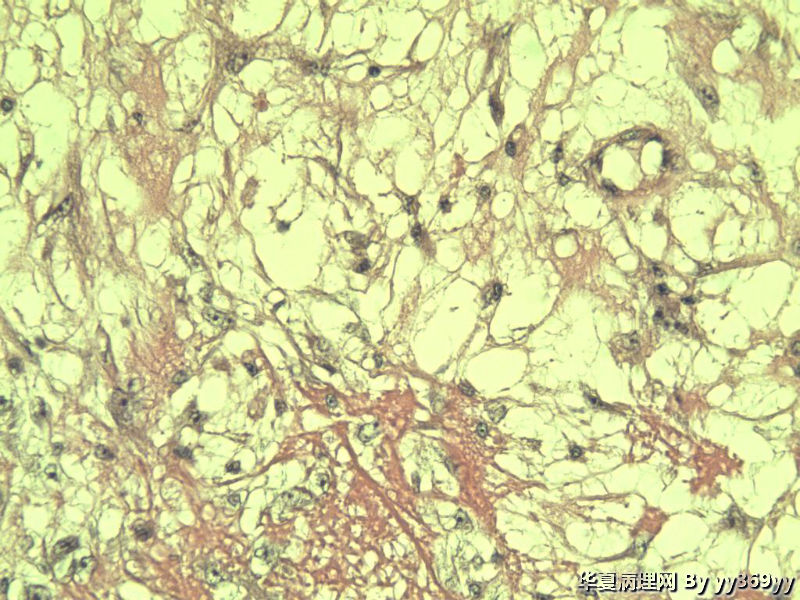

恶性的血管瘤??

男 30岁 小肠一段,肠管严重粘连可见一体积为 2.5 × 2 × 1.5 cm3的肿块,切面灰白,实性,质中

恶性的血管瘤??图3

肿块确切位置?图片颜色不正,需要考虑的有:脂肪坏死/腹腔纤维瘤病/炎性肌纤维母细胞瘤等。

纤维瘤病?

还有GIST需要鉴别